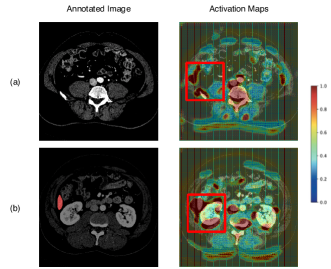

To show the effect of the attention network in our method, we visualize the activation maps extracted by the attention network. The activation maps of the images are shown in Figure 4.

From Figure 4(a), although the image does not have liver, the attention network also focuses on the location that is associated with the liver (the red box in Figure 4(a)). From Figure 4(b), it is easy to see that the attention network not only focuses on the liver that we need to segment, but also focuses on some part of the image around the liver (the red box in Figure 4(b)). According to the description above, it is easy to reach the conclusion that the surroundings of the target object are also useful for the classifier to distinguish the target object. Our local discriminator model can find out these useful surroundings.